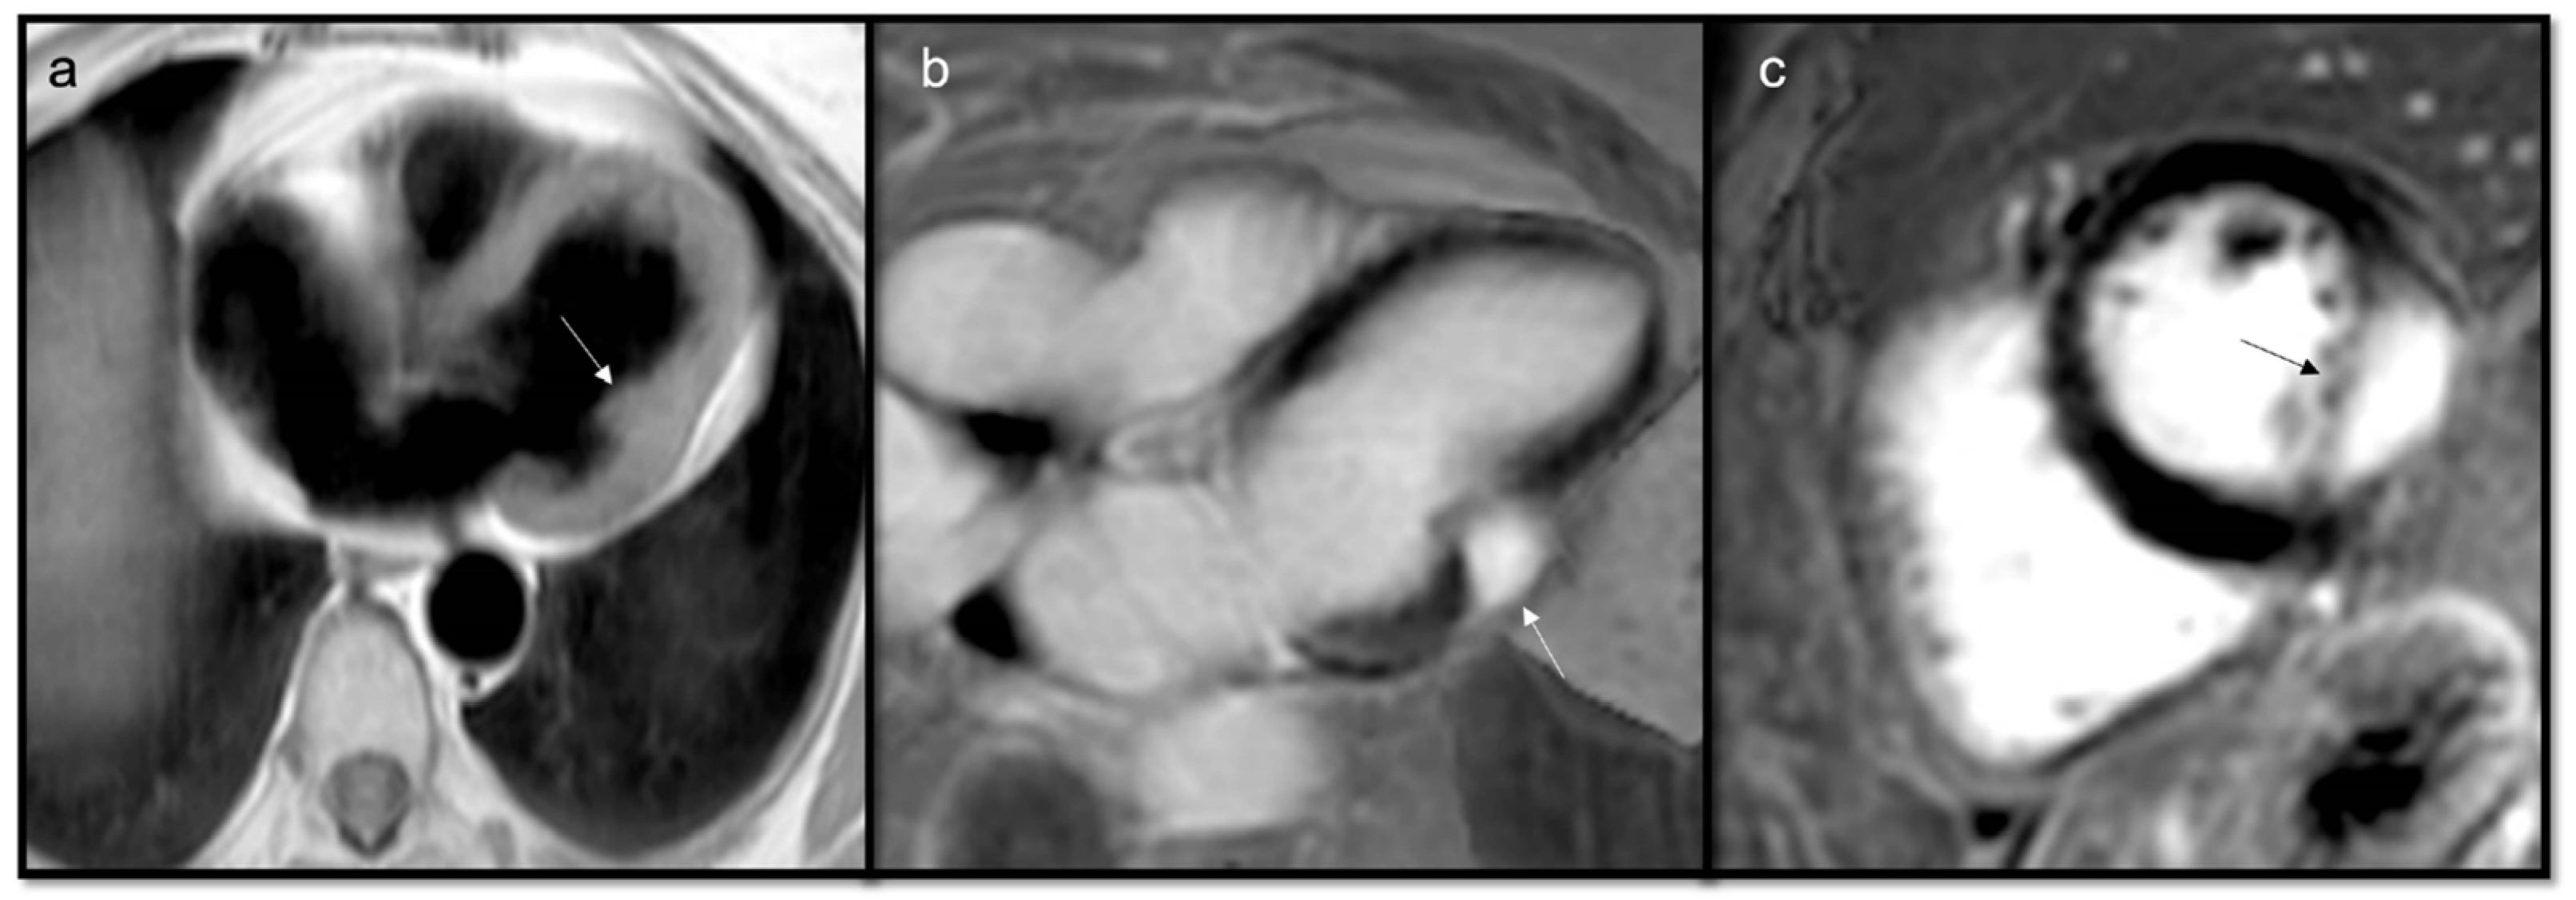

- To recognize fluid content such as a pericardial cyst or myocardial cyst (Figure 3)